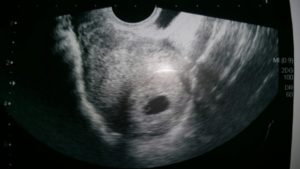

Однако ребенка на таком раннем этапе еще не видно – полноценного зародыша пока просто не существует. Поэтому ультразвук сможет показать будущего малыша в матке не раньше 3-5-й недель. На мониторе плодное яйцо смотрится как маленькая черная точка в маточной полости (обычно в верхней части). Сам эмбрион представляет собой небольшое образование белого цвета.

УЗИ 3 недели

УЗИ 4 недели